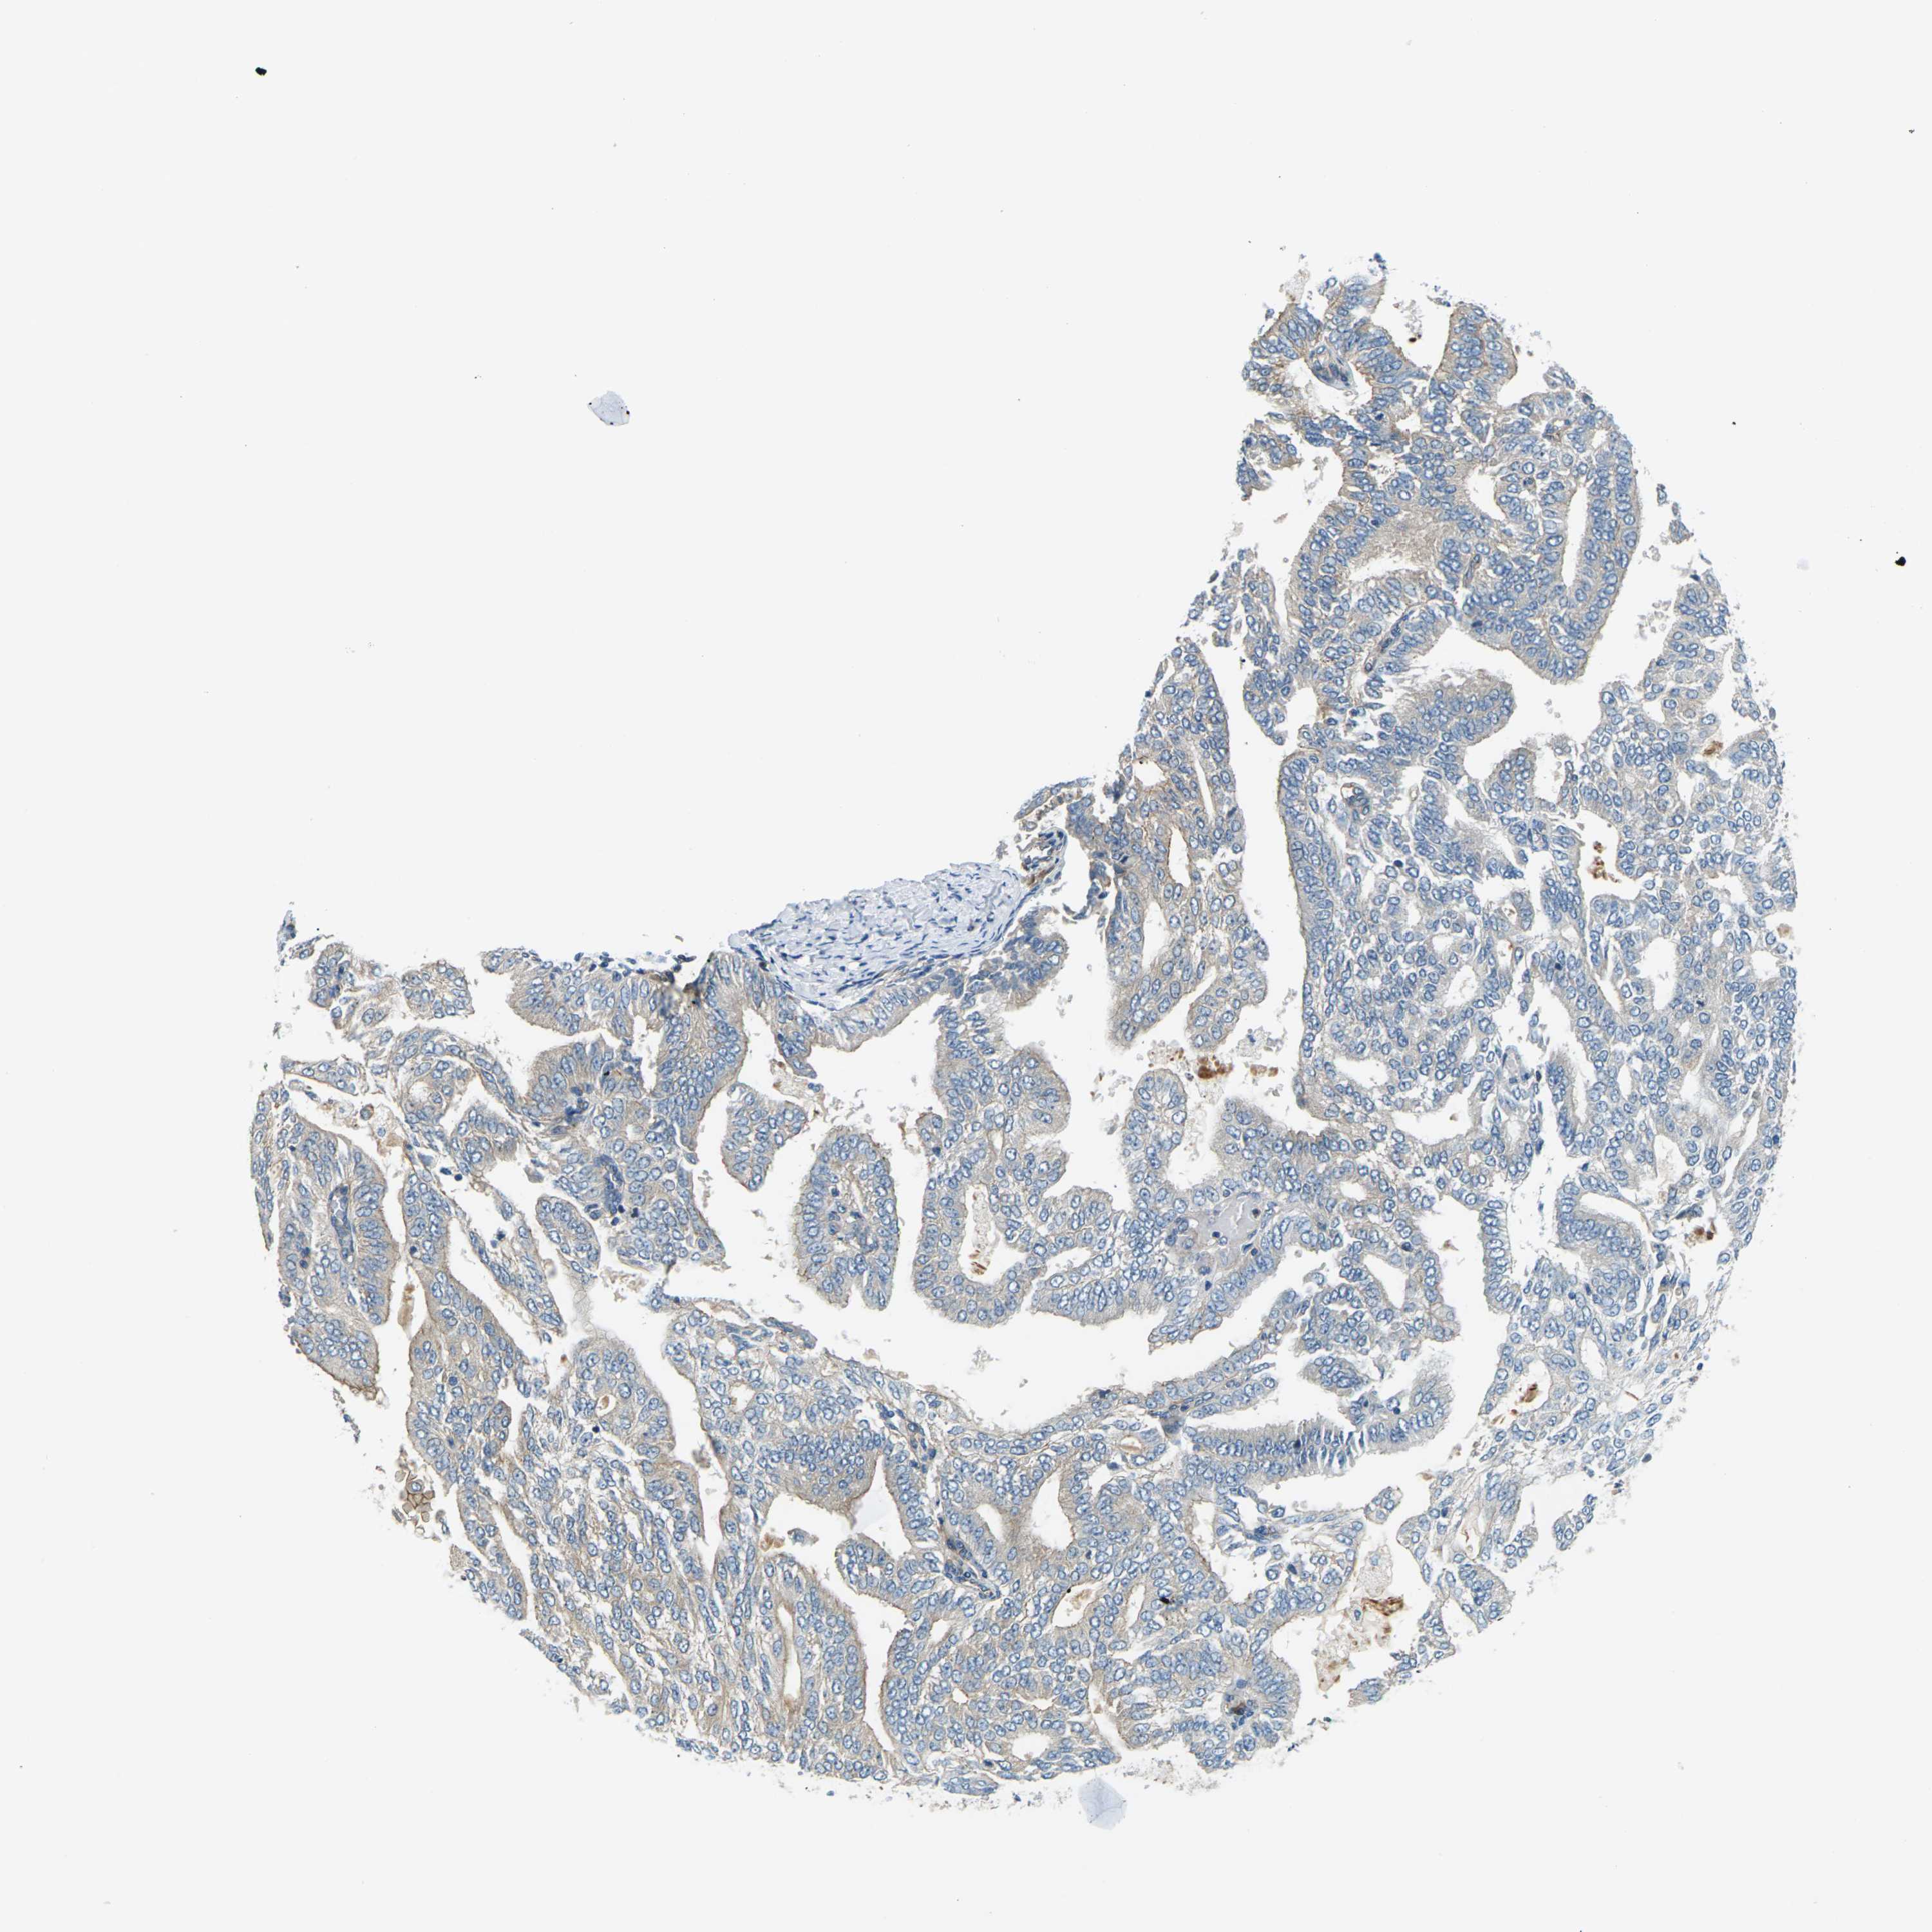

ENDOMETRIAL CANCER - Protein expressioni

A mouse-over function shows sample information and annotation data. Click on an image to view it in a full screen mode. Samples can be filtered based on level of antibody staining by selecting one or several of the following categories: high, medium, low and not detected. The assay and annotation is described here.

Note that samples used for immunohistochemistry by the Human Protein Atlas do not correspond to samples in the TCGA dataset.

Antibody stainingi

Antibody staining in the annotated cell types in the current human tissue is reported as not detected, low, medium, or high, based on conventional immunohistochemistry profiling in selected tissues. This score is based on the combination of the staining intensity and fraction of stained cells.

Each image is clickable and will lead to virtual microscopy that enables deeper exploration of all samples and also displays staining intensity scores, fraction scores and subcellular localization as well as patient and tissue information for each sample.

Antibody HPA014353

Antibody HPA014736

Staining

High

Medium

Low

Not detected

Intensity

Strong

Moderate

Weak

Negative

Quantity

>75%

75%-25%

<25%

None

Location

Nuclear

Cytoplasmic/membranous

Cytoplasmic/membranous,nuclear

Adenocarcinoma, NOS